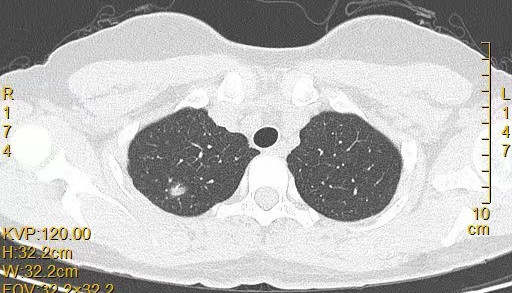

患者女,44岁,无特殊症状,做体检时发现右肺结节。查到1年前的体检CT片,右上肺当时就有一个直径约3mm的微小结节。两次检查检查图片如下:

以下9张为今年5.10的CT图片: